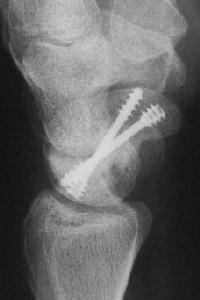

and healing.

Click for larger image